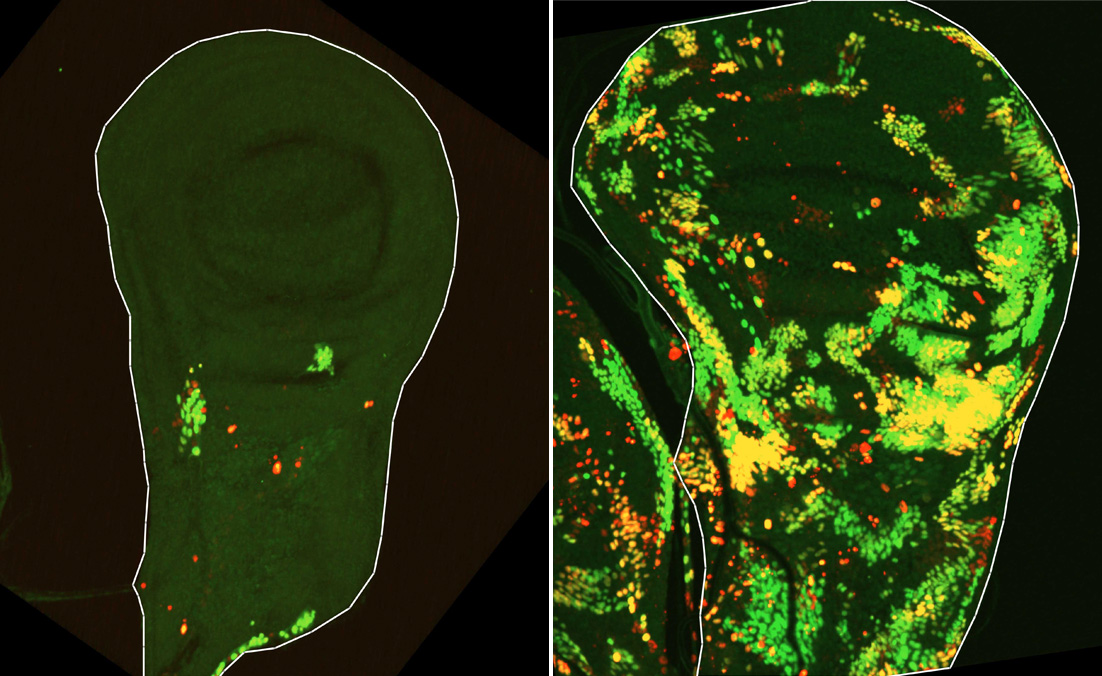

Tissu épithélial à partir duquel se développe l’aile de la mouche. Quatre heures après l’irradiation de ce tissu, on peut observer un petit nombre de cellules DARE résistantes à la mort qui ont survécu (à gauche, marquées en rouge). Après environ 24 heures, le nombre de ces cellules atteint son maximum, et après 48 heures, leurs descendantes (à droite, marquées en vert et jaune) repeuplent le tissu.